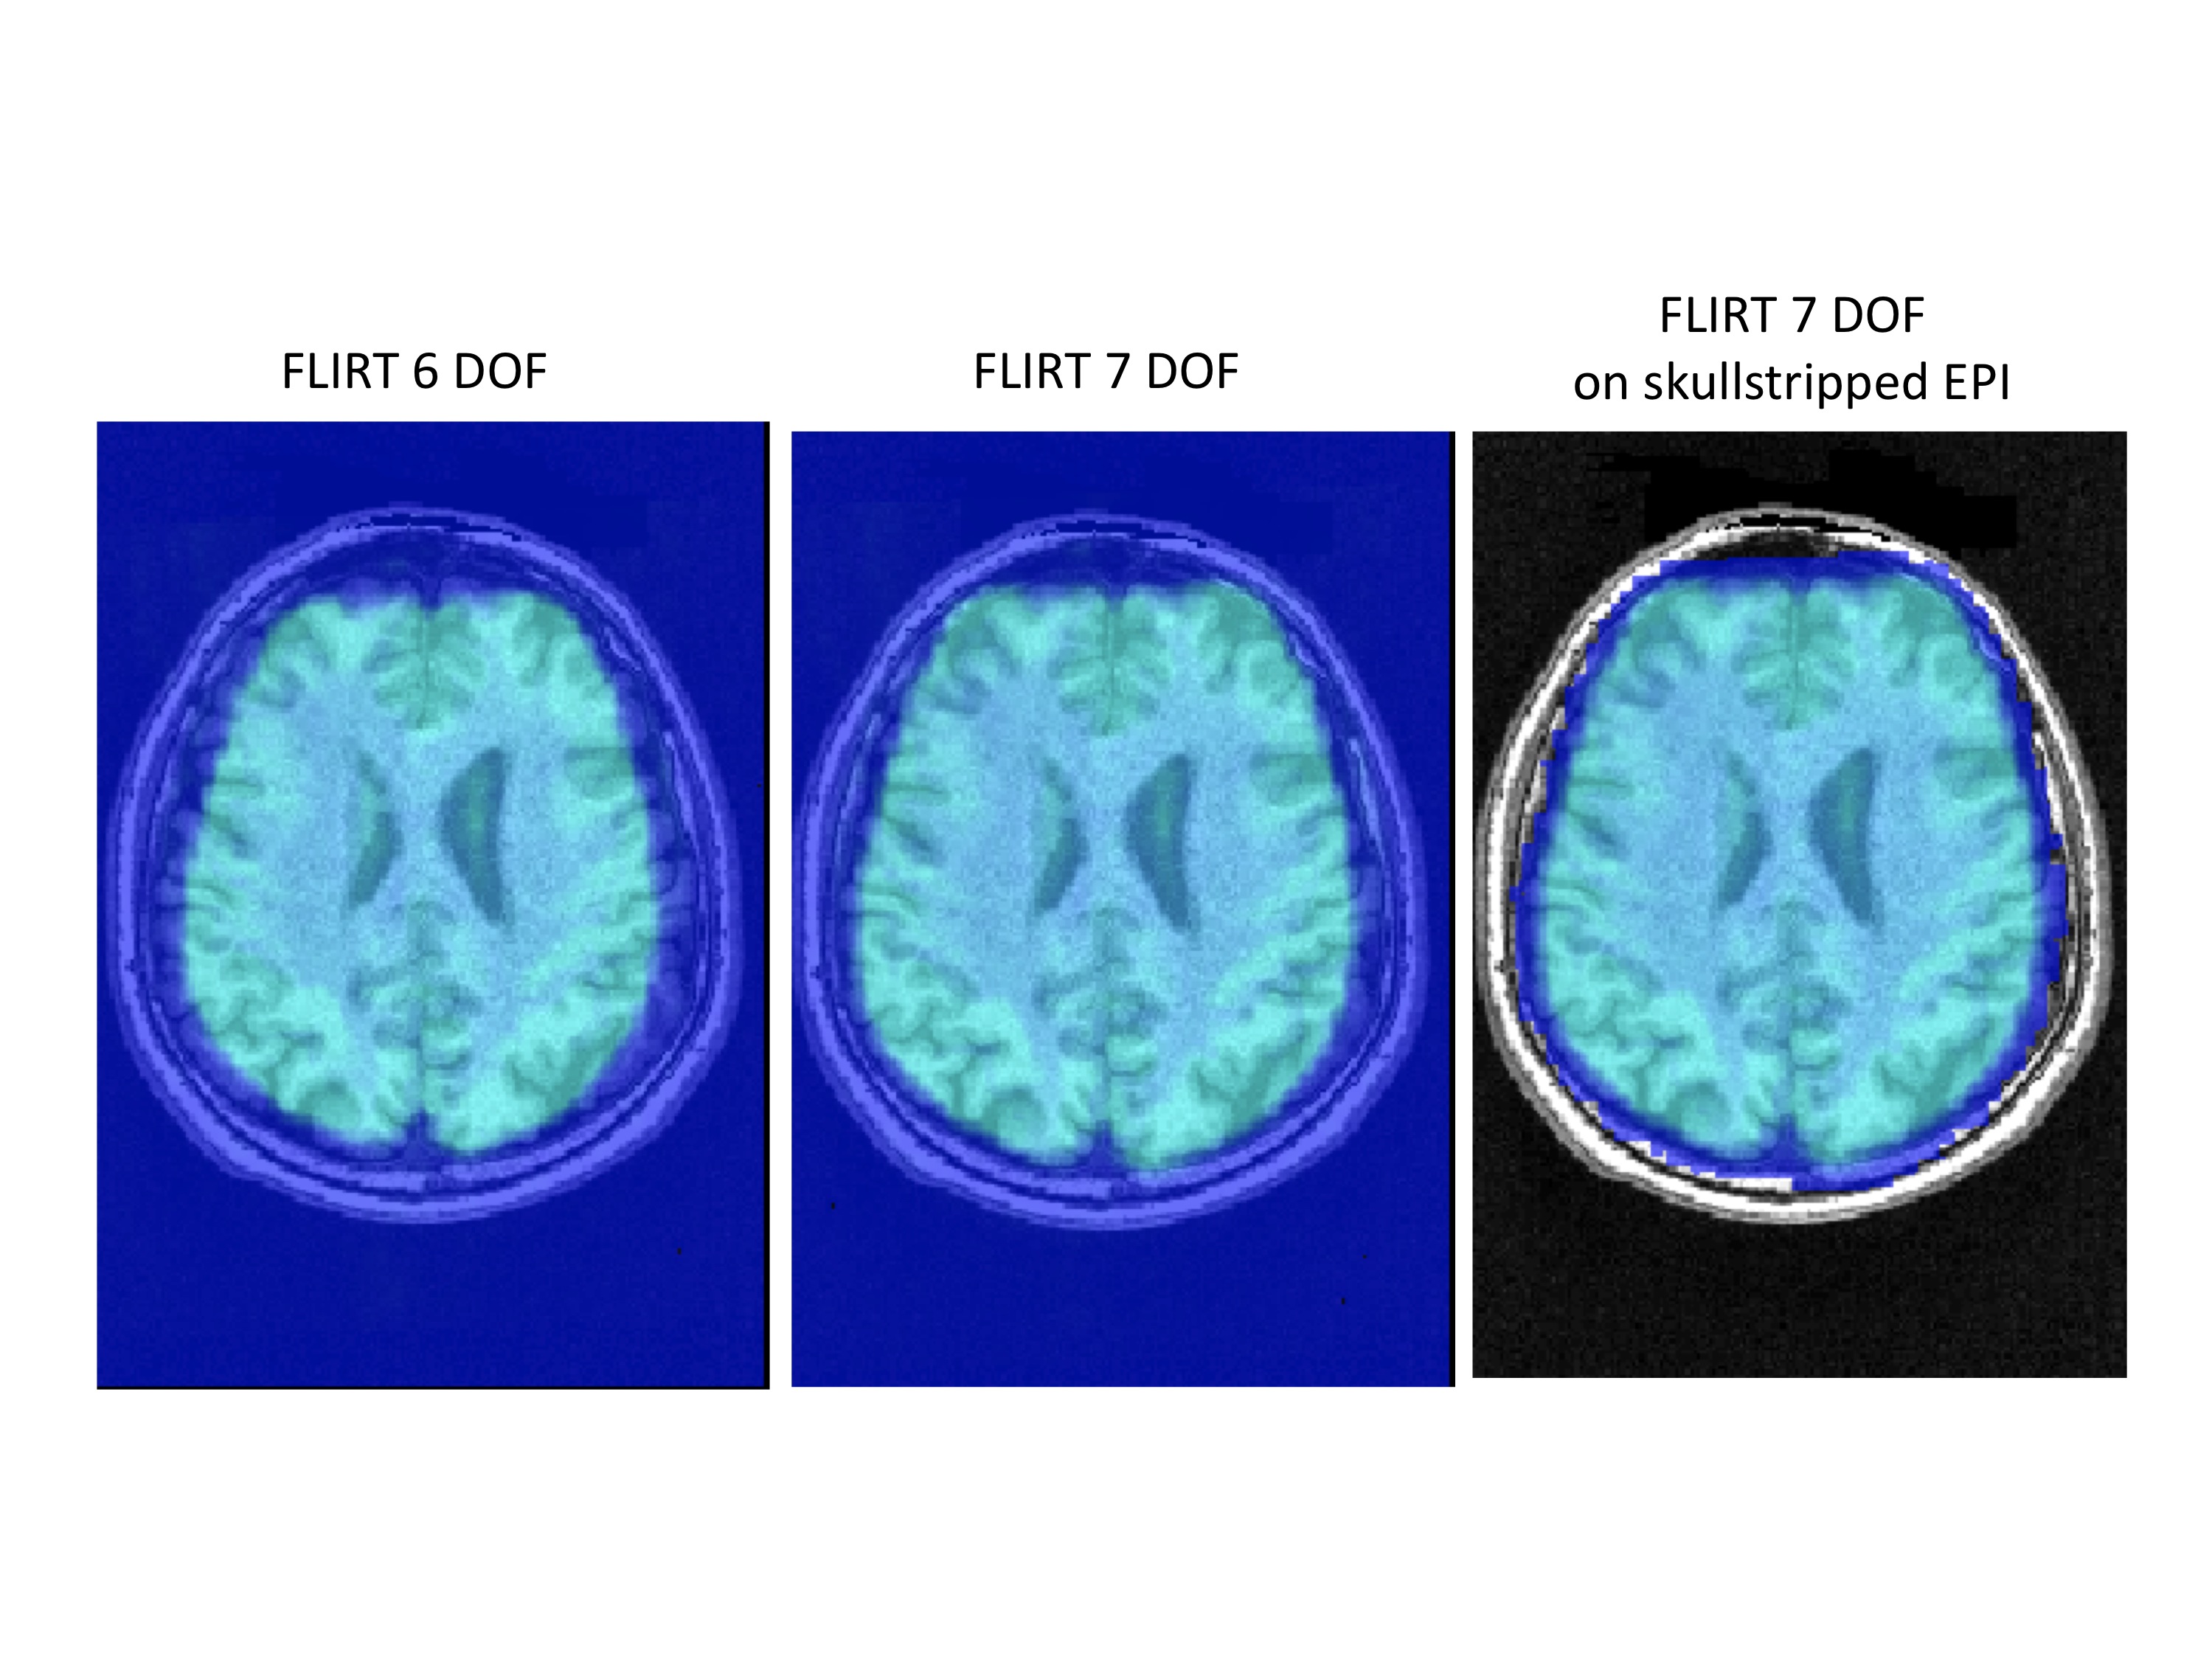

Regarding sub96591. We backtraced our steps and realized we used a 7 DOF linear EPI to skull-stripped MPRAGE for the images in the paper. However, the 7 vs. 6 DOF is not the full solution. If you look in our preprocessing scripts, you can see that we get the example func image that is used for later registration after skull-stripping the EPI. If you use the skull-stripped EPI in combination with the 7 DOF FLIRT registration the alignment appears to be good. I attached an image comparing 6 DOF to 7 DOF and 7 DOF on the skull-stripped EPI for this subject. The differences in results are pretty clear.

As to why 7 DOF appears to work better, one possibility is that some degree of scaling may have occurred for the EPI on the scanner. As indicated before, we are not sure whether the EPI and MPRAGE for these subjects were collected on the same day.